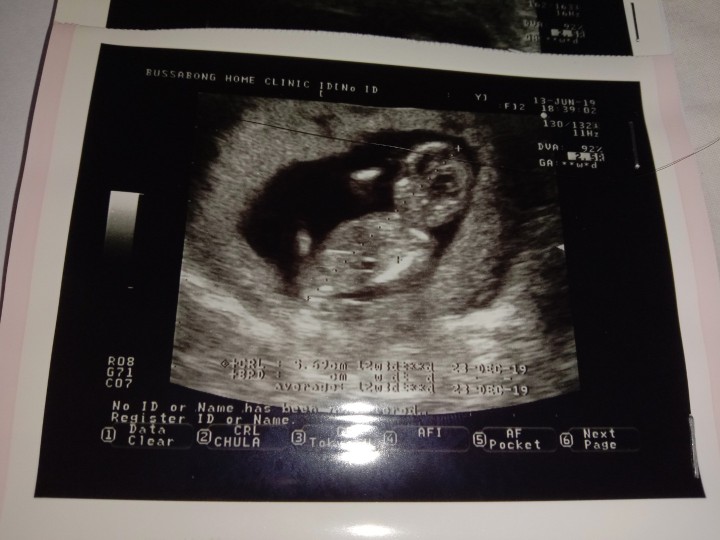

แม่บ้านนี้อยากได้ลูกสาวค่ะ #กำหนดคลอด 12 ธันวาคม #รูปซาวด์ตอน 12W